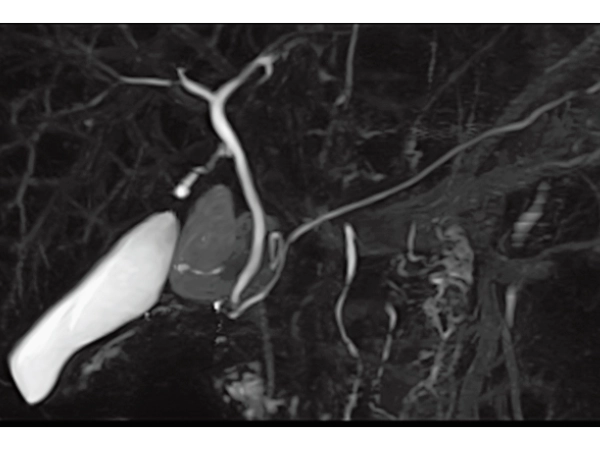

3DisoFSE MRCP (MIP)

Respiratory gating, 2:50

3D MRCPA (MIP)

Lower extremity

non-contrast MRA (MIP)